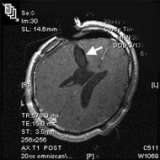

- Magnetic resonance imaging (MRI) is the preferred diagnostic tool, although the diagnosis should be confirmed by microscopic examination of the tumor from a biopsy.

- Sometimes, ependymomas are best removed with the aid of intra-operative MRI, allowing the most complete, safest surgery possible.

This post-operative MRI (above) confirms image-complete removal of the tumor. - Radiation Therapy